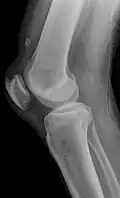

Quadriceps tendon rupture in plain X-ray -